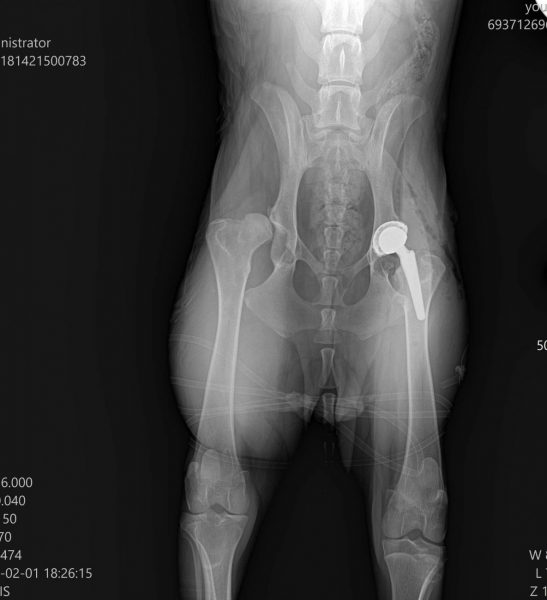

Η ακτινογραφία του μετά το χειρουργείο. Δεξιά φαίνεται η τεχνητή ενδοπρόθεση

Κατά την επέμβαση αφαιρείται η πάσχουσα άρθρωση και αντικαθίσταται με τεχνητή ενδοπρόθεση, συνήθως από τιτάνιο.